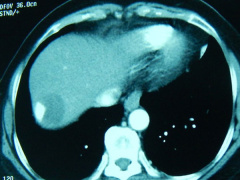

Loại bỏ khối u gan khổng lồ ở bệnh nhân nữ 67 tuổi

Bệnh viện Nhân dân 115 TP HCM vừa phẫu thuật loại bỏ thành công khối u gan kích thước 6x7 cm để cứu một người phụ nữ.